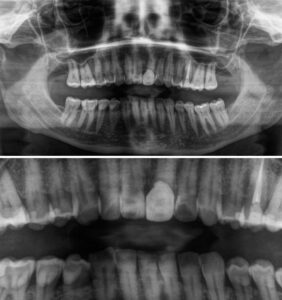

Extracción de las Muelas del Juicio 23 noviembre, 2023 La extracción de las muelas del juicio suele ser una de las operaciones más habituales que se realizan en una clínica dental.

Centro de Radiología en Carabanchel 6 noviembre, 2023 Nuestra clínica dispone de la aparatología necesaria para ser tu centro de referencia de radiología en Carabanchel.